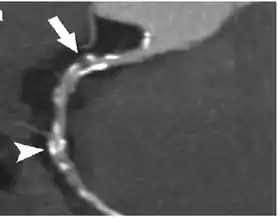

Coronary Computed Tomography Angiography (CCTA)

Computed tomography angiography (CTA), an imaging methodology using a ring-shaped machine with an X-ray source spinning around the circular path so as to bathe the inner circle with a uniform and known X-ray density. Cardiology uses are growing with the incredible developments in CT technology. Currently, multidetector CT, specially the 64 detector-CT are allowing to make cardiac studies in just a few seconds (less than 10 seconds, depending on the equipment and protocol used). These images are reconstructed using algorithms and software.

Coronary CT calcium scan

A coronary CT calcium scan is a computed tomography (CT) scan of the heart for the assessment of severity of coronary artery disease. Specifically, it looks for calcium deposits in the coronary arteries that can narrow arteries and increase the risk of heart attack.[17] This severity can be presented as Agatston score or Coronary Artery Calcium (CAC) score. The CAC score is an independent marker of risk for cardiac events, cardiac mortality, and all-cause mortality.[18] In addition, it provides additional prognostic information to other cardiovascular risk markers.[18] A typical coronary CT calcium scan is done without the use of radiocontrast dye, but it can possibly be done from contrast-enhanced images as well, such as in coronary CT angiography.[19]